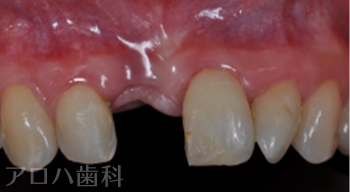

CASE01/60代女性

初診時

治療終了後3年時

| 主訴 | 左の前歯が折れた |

| 治療内容 | 左上前歯にお痛みがあり、土台を外したところ、破折により抜歯となった方です。 骨が薄かったため、抜歯と同時にインプラントを行う【抜歯即時インプラント】を行いました。 インプラント治療により歯があったときと変わらない状態に回復しました。 |

| 治療期間 | 1週間 |

| 治療費用 | 627,000円 |

| 費用詳細 | ・TEC 22,000円 ・サージカルガイド 55,000円 ・GBR 110,000円 ・インプラント手術+アバットメント+上部構造 440,000円 |